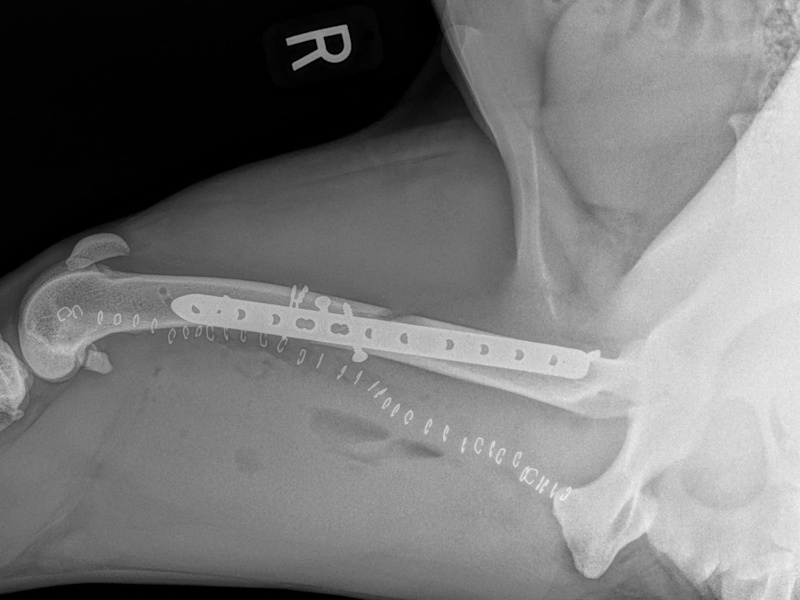

Tibial Plateau Leveling Osteotomy (TPLO) - additional information

An osteotomy is a surgical cut in a bone. In the cruciate deficient stifle, a cut is made in the top of the tibia. The top portion of bone that contains the articular surface is rotated to level it. The two pieces of bone are held in place with a metal plate and screws.

Post Surgical Radiographs

While the patient is still anesthetized, the patient is taken into radiology for post-surgery radiographs (X-rays). The radiographs are assessed to measure the new tibial plateau angle. We are aiming for 5-6 degrees relative to the long axis of the tibia. The apparatus (plate and screws) are assessed for size and appropriate position.